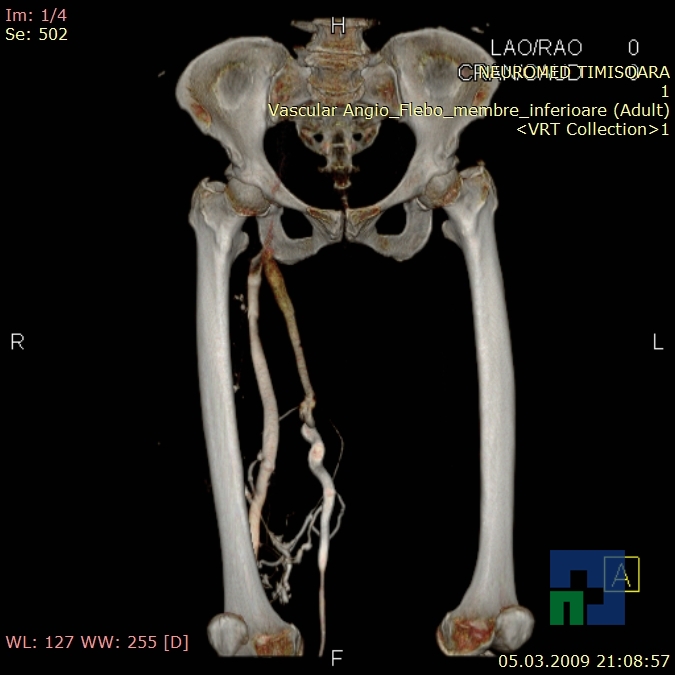

- Fistula carotido-cavernoasa